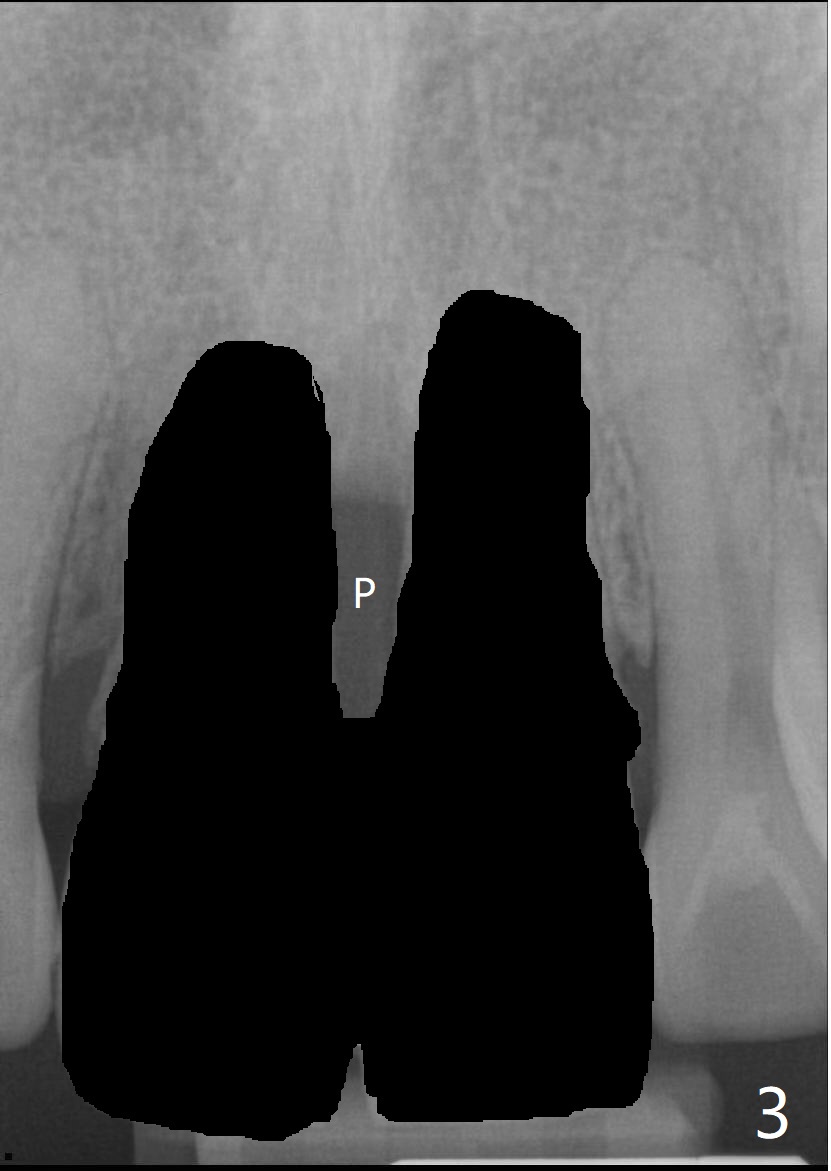

40几岁,身体无其它疾病(图一),全面检查,包括CT,取模做suck down stent/临时牙冠。第一种方法,保留一个牙根(图二:例如8号牙),减少两个牙齿之间软硬组织萎缩,一个植牙(绿色,至鼻底),基台(粉红色),临时悬臂桥,植体周围以及龈乳头下植骨(红圆圈)。图三显示两个牙齿都拔除,P:龈乳头,缺骨。为了在龈乳头下面植骨,分离它的根部,往冠方推移(图四:箭头),在产生的空间里放置骨粉(红圆圈)。也可以在颊侧近中保留部分牙根(socket shield,图五:S),然后游离龈乳头根部,推移,植骨(图六),最后植入两个植体。